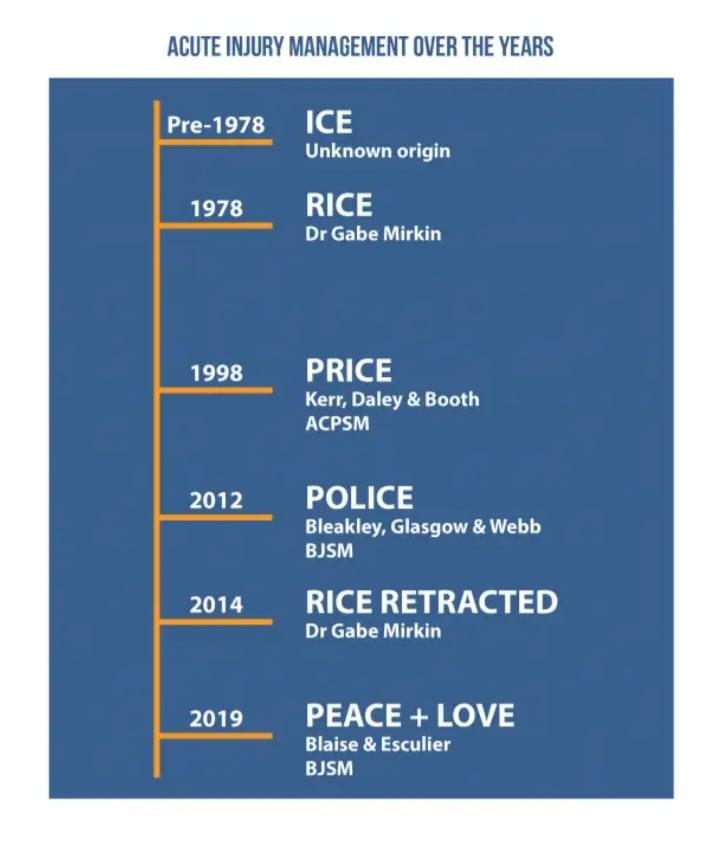

Η ιστορία της Διαχείρησης του Διαστρέμματος, PEACE & LOVE, γράφει ο Γκέλσης Ιωάννης,PT,OMT,Acup.sp

Το «αιώνιο» ερώτημα; Να βάλω πάγο στο διάστρεμμα της ποδοκνημικής μου (στραμπούλιγμα αστραγάλου) ; Εξαρτάται σε ποια εποχή ζεις, είναι η σωστή απάντηση! Η επιστημονική έρευνα, μας δίνει συνεχώς νέα δεδομένα και αποδείξεις οπότε όλα αλλάζουν και προσαρμόζονται συνεχώς, έτσι αναπτυσσόμαστε και εξελισσόμαστε κατά την διάρκεια της παρουσίας...